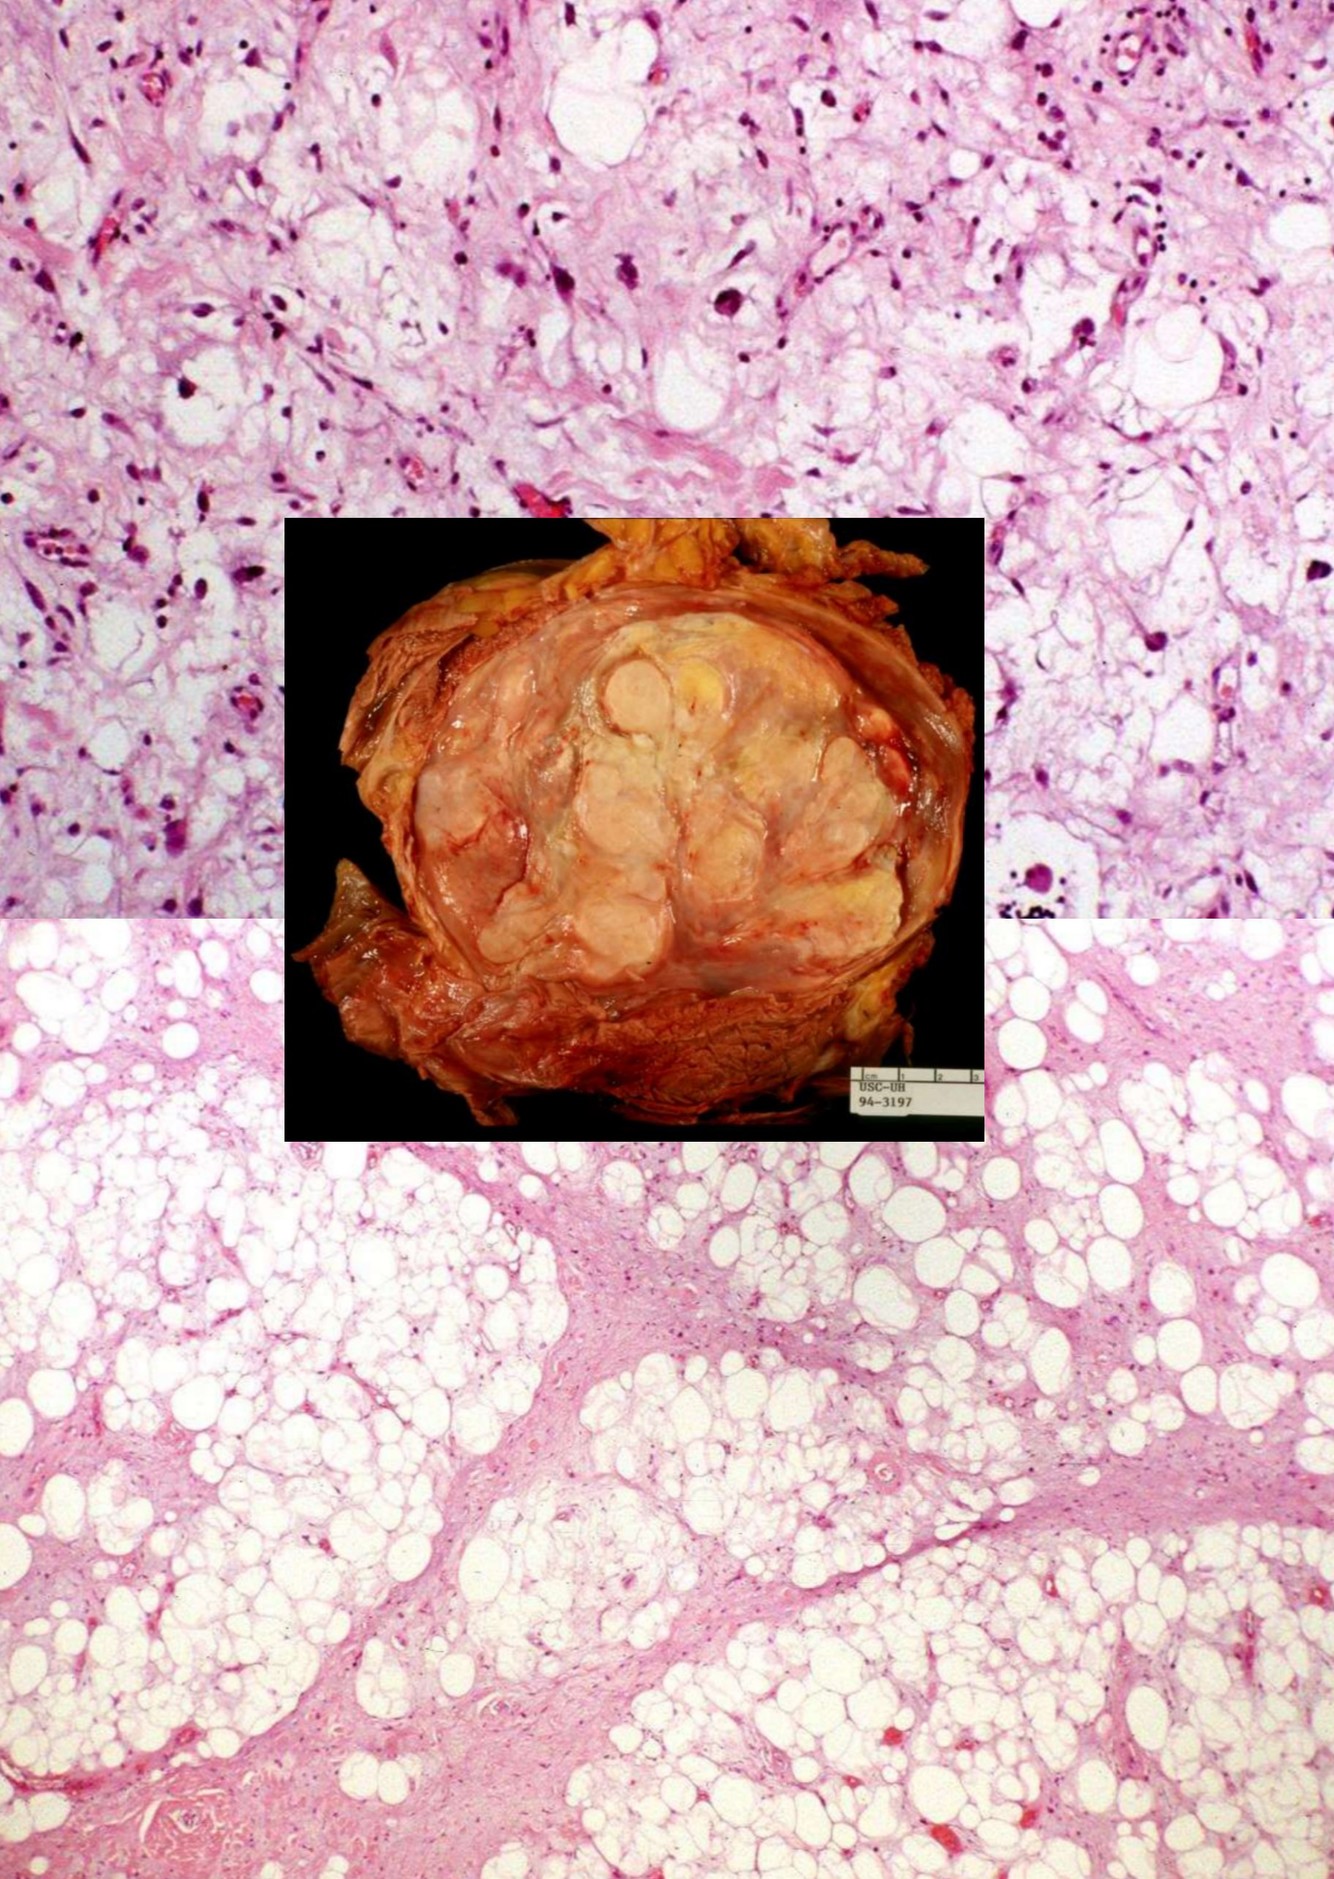

ATYPICAL LIPOMATOUS TUMOR / WELL-DIFFERENTIATED LIPOSARCOMA

• One of the most common soft tissue sarcoma of adulthood

• lower extremities and retroperitoneum

• Genetics:

• Ring or giant marker/rod chromosomes derived from 12q13-15 in almost all cases

• Amplifications of the 12q12-21 and 10p11-14 regions

• MDM2 and CDK4 by FISH or real time PCR can differentiate from other sarcomas

• Carboxypeptidase M amplification may be alternative diagnostic tool

• Other rearrangements include amplifications of 12q12-21 and 10p11-14 regions

• Histology

• Mature fat plus variably sized adipocytes and fibromyxoid stroma containing spindle cells with large, deep-staining nuclei and marked nuclear enlargement or pleomorphism

• Cellularity is low and mitotic figures are uncommon

• Usually fibrous tissue septa are present that may contain spindle cells or highly pleomorphic cells

• Some nuclei have sharply outlined vacuoles (Lochkern)

• Rarely heterologous differentiation

• No/few lipoblasts

• May be associated with metaplastic bone formation

• Rarely has low grade osteosarcomatous component

• Includes lipoma-like and sclerosing variants

• Stains:

• Postive: MDM2 and CDK4 (both together are sensitive and specific, S100 (adipocytes in 2/3 of cases), CD34 (some spindle cells), Usually p16

• Negative: HMB45